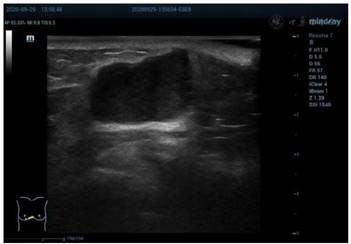

乳腺超声显示(图1):右侧乳腺5点半距乳头8~10 cm腺体边缘近胸骨旁扫见混合回声结节,大小约26 mm×15 mm,距体表6 mm,边界清晰,形态欠规则,内部回声欠均匀,后方回声略增强,CDFI:可见少许血流信号(图2)。弹性成像显示肿块硬度尚可(图3)诊断为BI-RADS 4a类,建议行乳腺超声造影。行超声造影后提示:增强早期肿块与周围乳腺组织相比,造影剂呈向心性、快进、高增强(图4),分布均匀,周边未见明显滋养血管,造影后范围30 mm×17 mm,大于二维超声;增强晚期造影剂缓慢消退,诊断为BI-RADS 4c类。